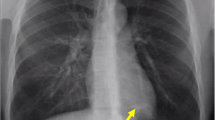

A medicolegal autopsy was performed the day after. According to police investigations, the diving equipment did not show any dysfunction. Post-mortem computed tomography (PMCT) revealed diffuse bilateral interstitial thickening, panlobar air space consolidations in the anterior segments of each lobe (Fig. 1), and pulmonary emphysema.

The diagnosis relies on clinical history (beginning of symptoms during the dive and worsening during ascent, cough, frothy sputum, and haemoptysis) [5]. Furthermore, pulmonary CT scan shows ground glass opacities, dilatation of pulmonary veins, interlobular thickening, and/or pleural effusion [6]. Ground glass opacities and interlobular thickening may demonstrate a patterned distribution [5,6,7], likely in the anterior segments of both lungs as in the case described above. This can be explained by the manifestation of pulmonary lesions in a sloping position (areas of greater transmural pressure during the dive) combined with the horizontal position of the diver in the water [6]. Blood testing (whether ante- or post-mortem) includes cardiac biomarkers (troponins, BNP), which are usually elevated (as opposed to decompression sickness) [3, 10]. However, normal levels of these biomarkers do not exclude the diagnosis, since their elevation takes several hours [2, 3].

IPE is a rare and underestimated pathology in scuba diving and swimming activities, but it can lead to a fatal issue. Post-mortem diagnosis of IPE is challenging. It rests on police investigation (technical expertise in order to exclude malfunction of diving devices, diving profile analysis, audition of witnesses, water temperature), access to medical information (classical cough, frothy sputum and haemoptysis, worsening during ascent), complete medicolegal autopsy (including histological examination, notably of the lungs) to exclude alternative cause of death, signs of drowning and assess comorbid conditions, and toxicological analysis. PMCT is an important diagnosis tool and shows characteristic ground glass opacities and interlobular thickening of the lungs, often demonstrating a distribution in the anterior segments of both lungs.